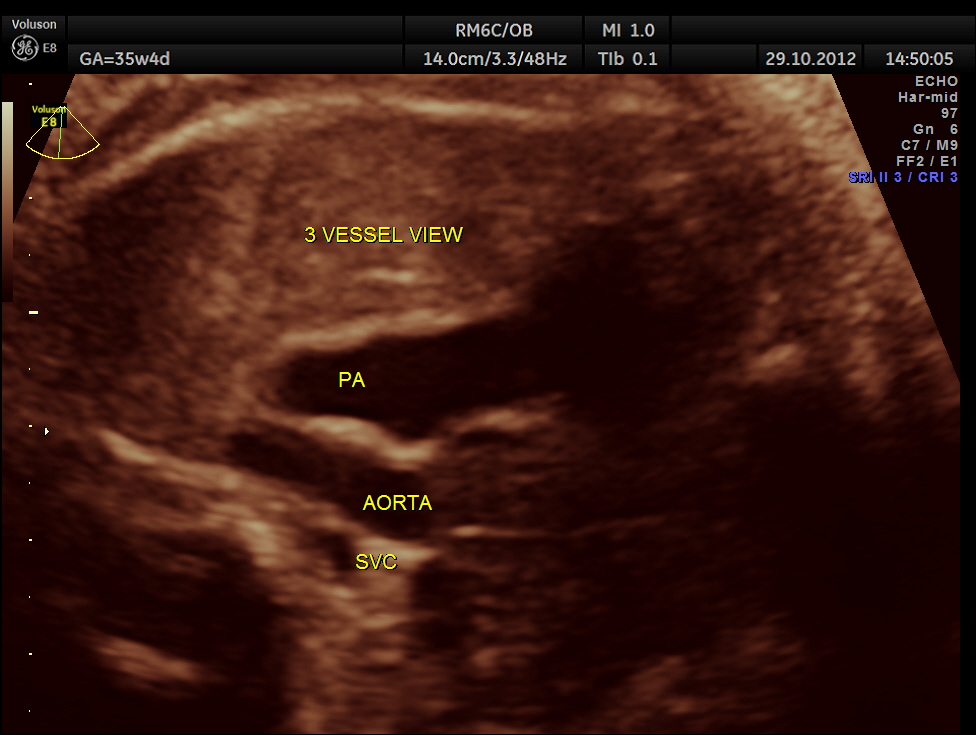

the important views of the heart are shown below